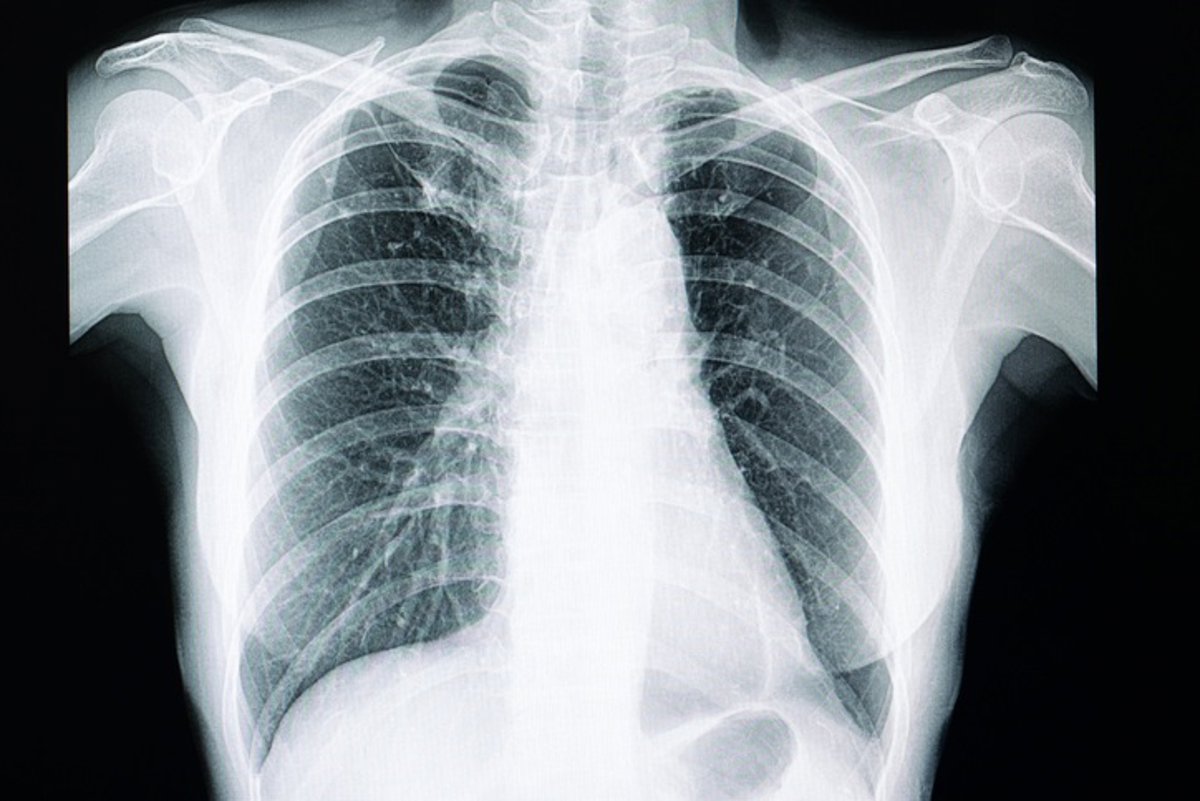

Archivo - Arquivo - Pulmões, radiografia de tórax

GETTY IMAGES/ISTOCKPHOTO / - Arquivo